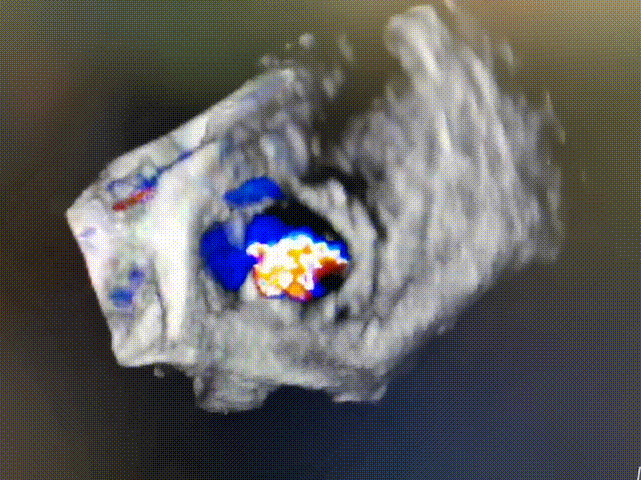

术后食道超声和造影显示,介入瓣支架固定,释放位置满意,瓣叶启闭形态未见异常,彩色多普勒未测及介入瓣内异常反流,估测瓣口面积约3.4cm²,前向峰值流速0.9m/s,峰值压差3mmHg,平均压差2mmHg。C形人工瓣环开口处与介入瓣之间有轻度瓣周漏,与术前预判一致。

术后心超